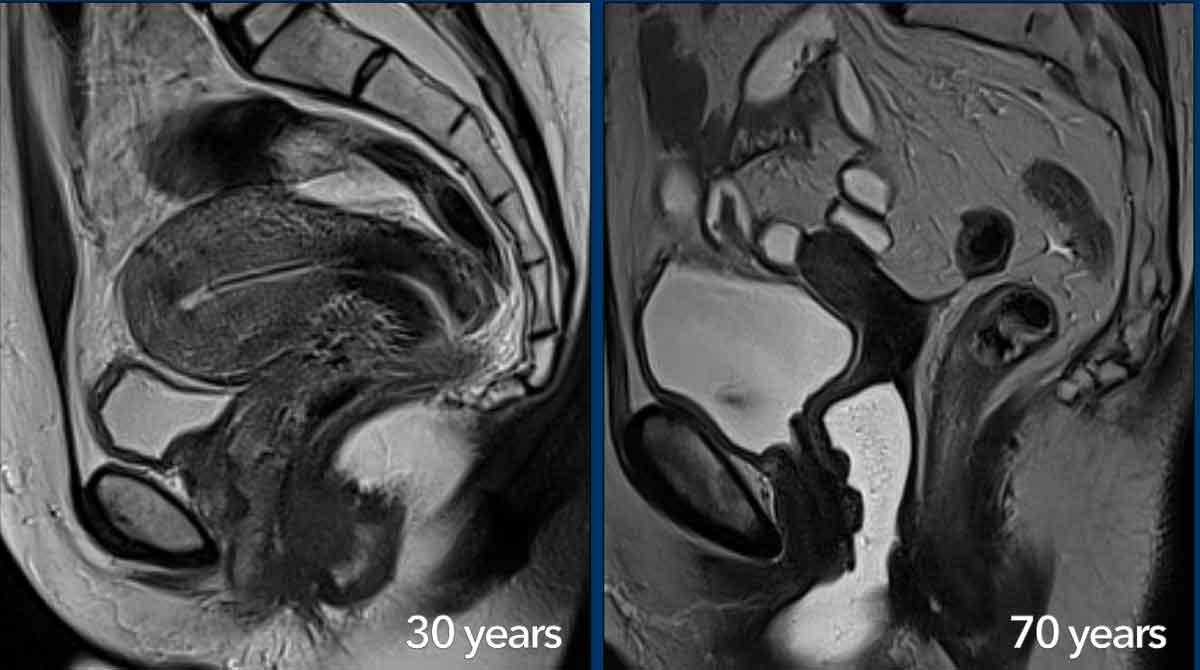

Giải phẫu theo vùng trên MRI của tử cung và cổ tử cung thay đổi theo độ tuổi.

Trong độ tuổi sinh sản, các lớp khác nhau của tử cung và cổ tử cung có thể được nhận diện rõ ràng và phần cơ của thành tử cung có thể được tưới máu phong phú.

Ở người phụ nữ 30 tuổi này, có sự hiện diện của dụng cụ tử cung (IUD) trong buồng tử cung (được nhận diện là cấu trúc tuyến tính giảm tín hiệu).

Ở phụ nữ sau mãn kinh, giải phẫu theo vùng trở nên kém rõ ràng hơn và mô đệm cổ tử cung, vùng tiếp hợp cũng như lớp cơ tử cung có biểu hiện giảm tín hiệu đồng nhất hơn trên chuỗi xung T2W.

Theo tuổi tác, các cơ quan sinh dục nữ dần thu nhỏ lại, trong đó tử cung mất thể tích nhiều hơn so với cổ tử cung.